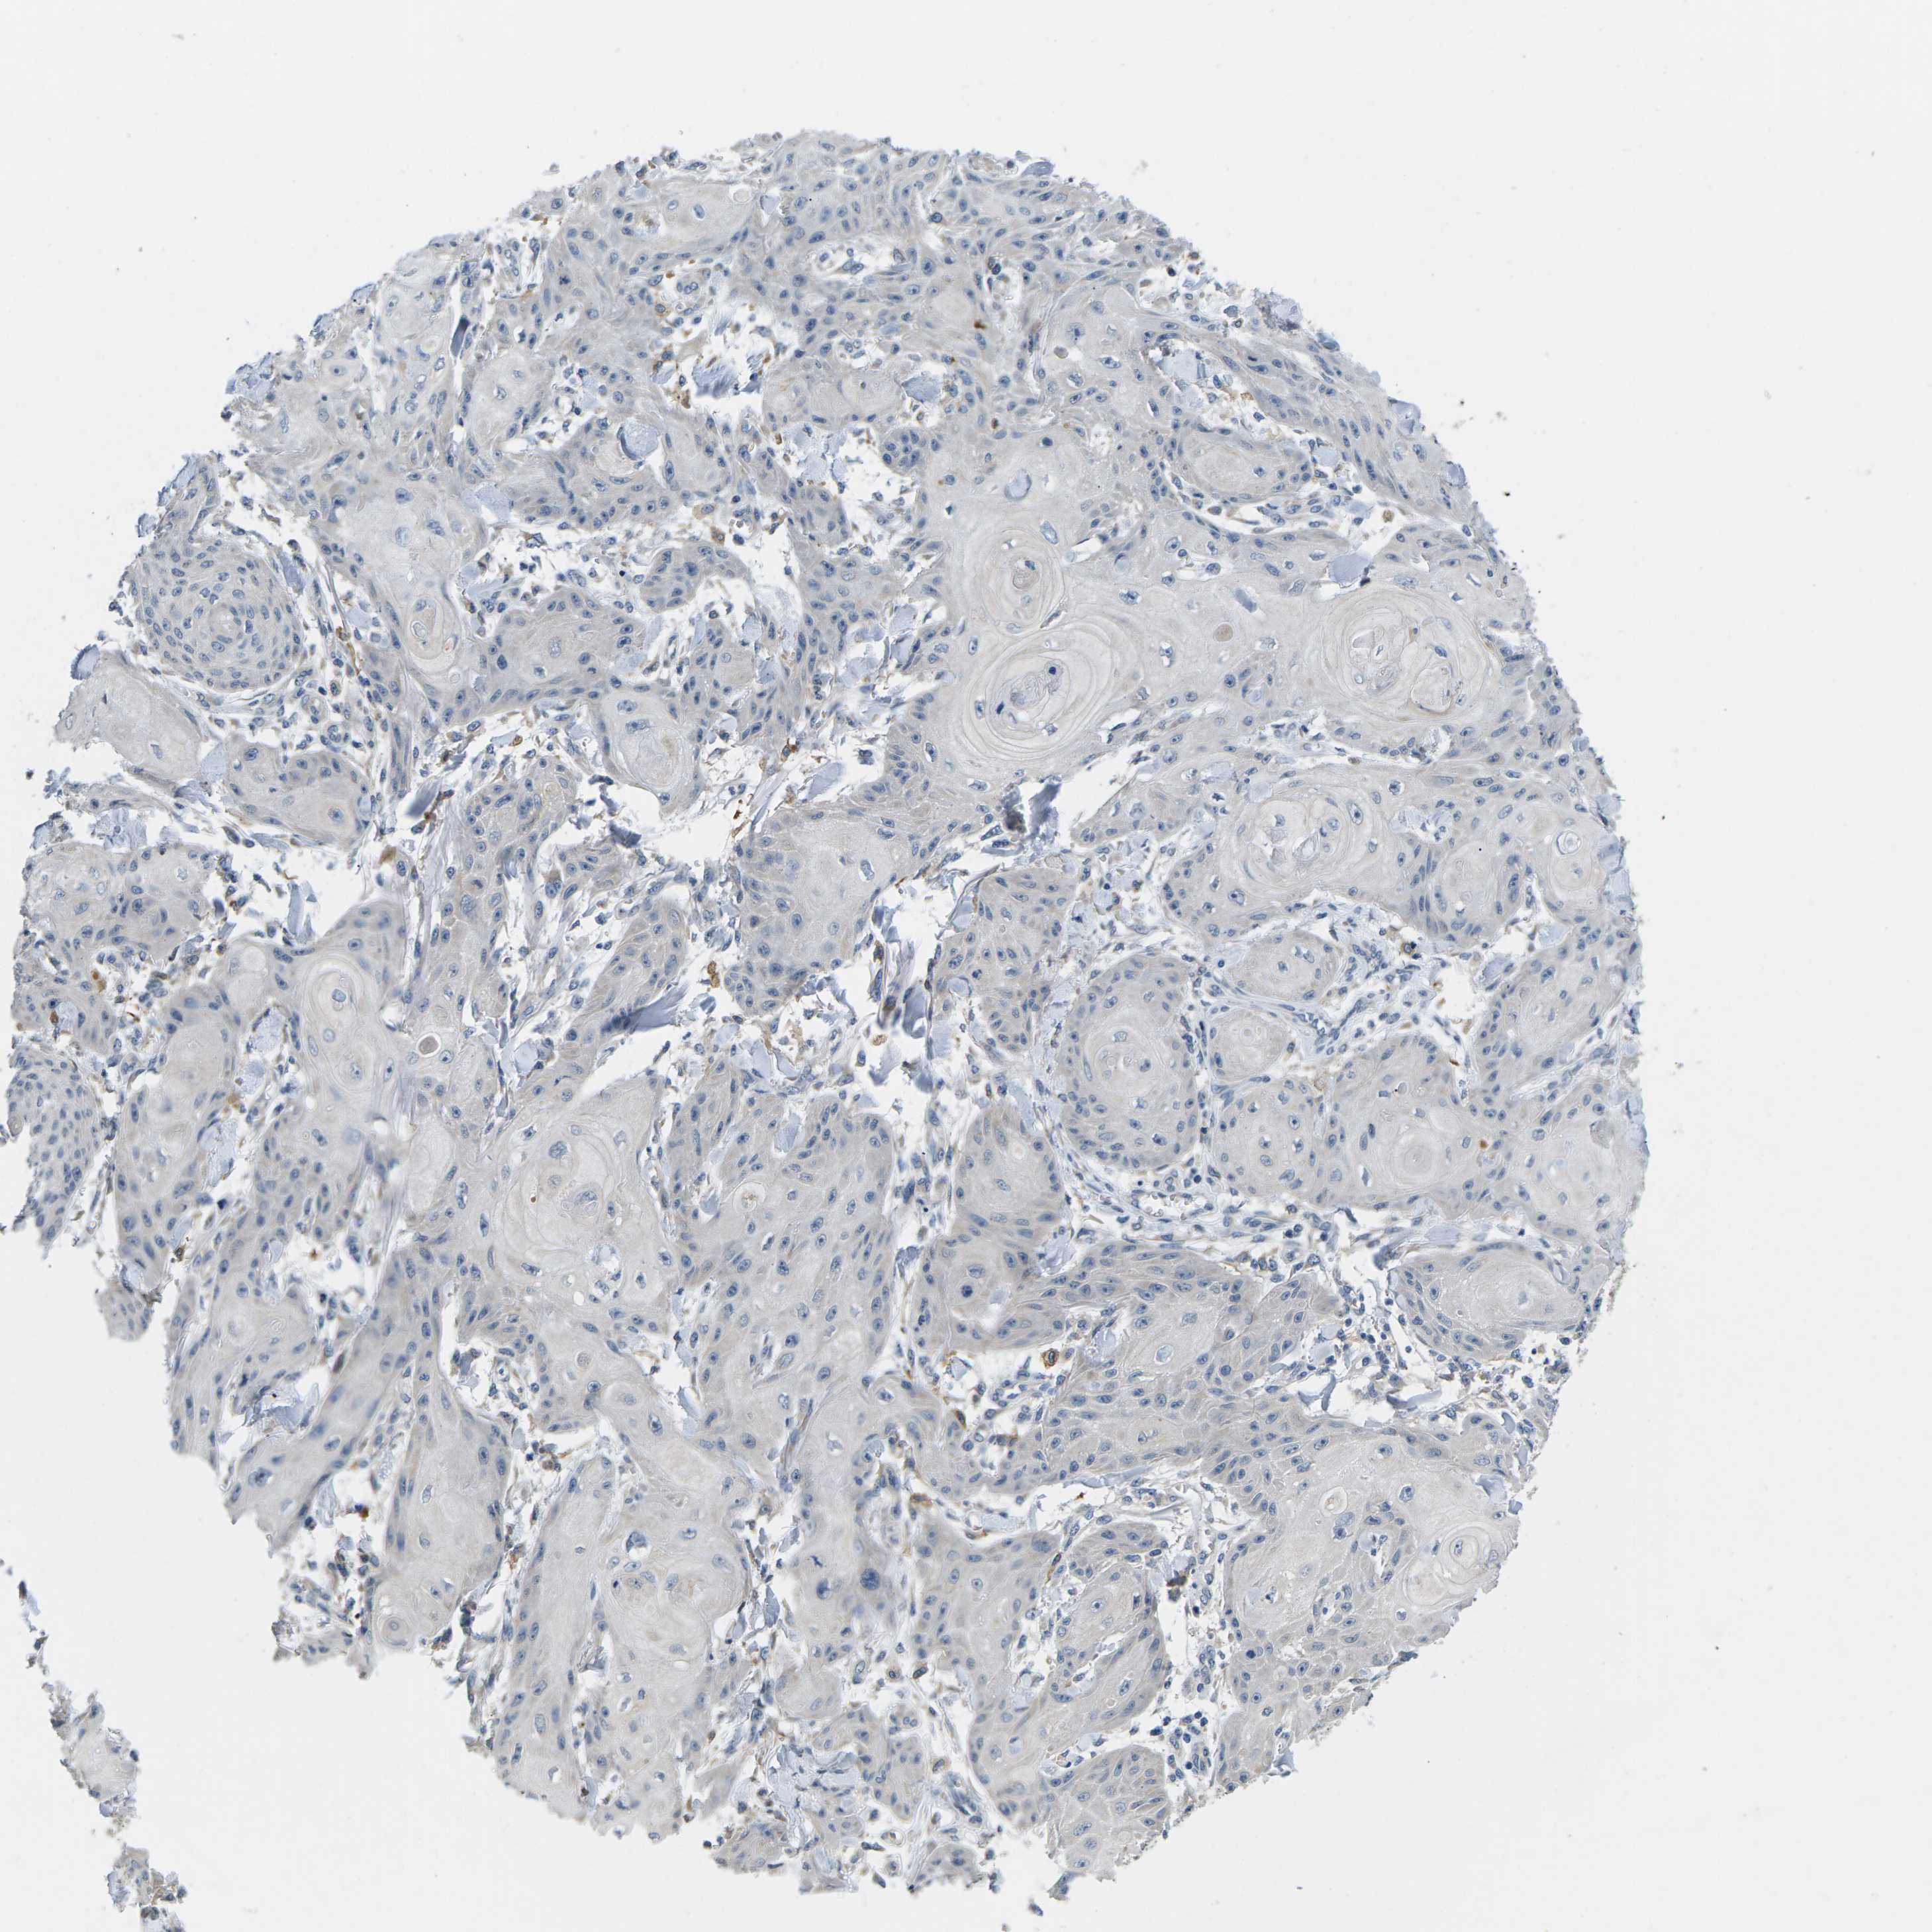

Basal cell and squamous cell cancer

SKIN CANCER - Protein expressioni

A mouse-over function shows sample information and annotation data. Click on an image to view it in a full screen mode. Samples can be filtered based on level of antibody staining by selecting one or several of the following categories: high, medium, low and not detected. The assay and annotation is described here.

Each image is clickable and will lead to virtual microscopy that enables deeper exploration of all samples and also displays staining intensity scores, fraction scores and subcellular localization as well as patient and tissue information for each sample.

Antibody HPA015968

Squamous cell carcinoma in situ, NOS

Squamous cell carcinoma, NOS

Adnexal tumor, benign